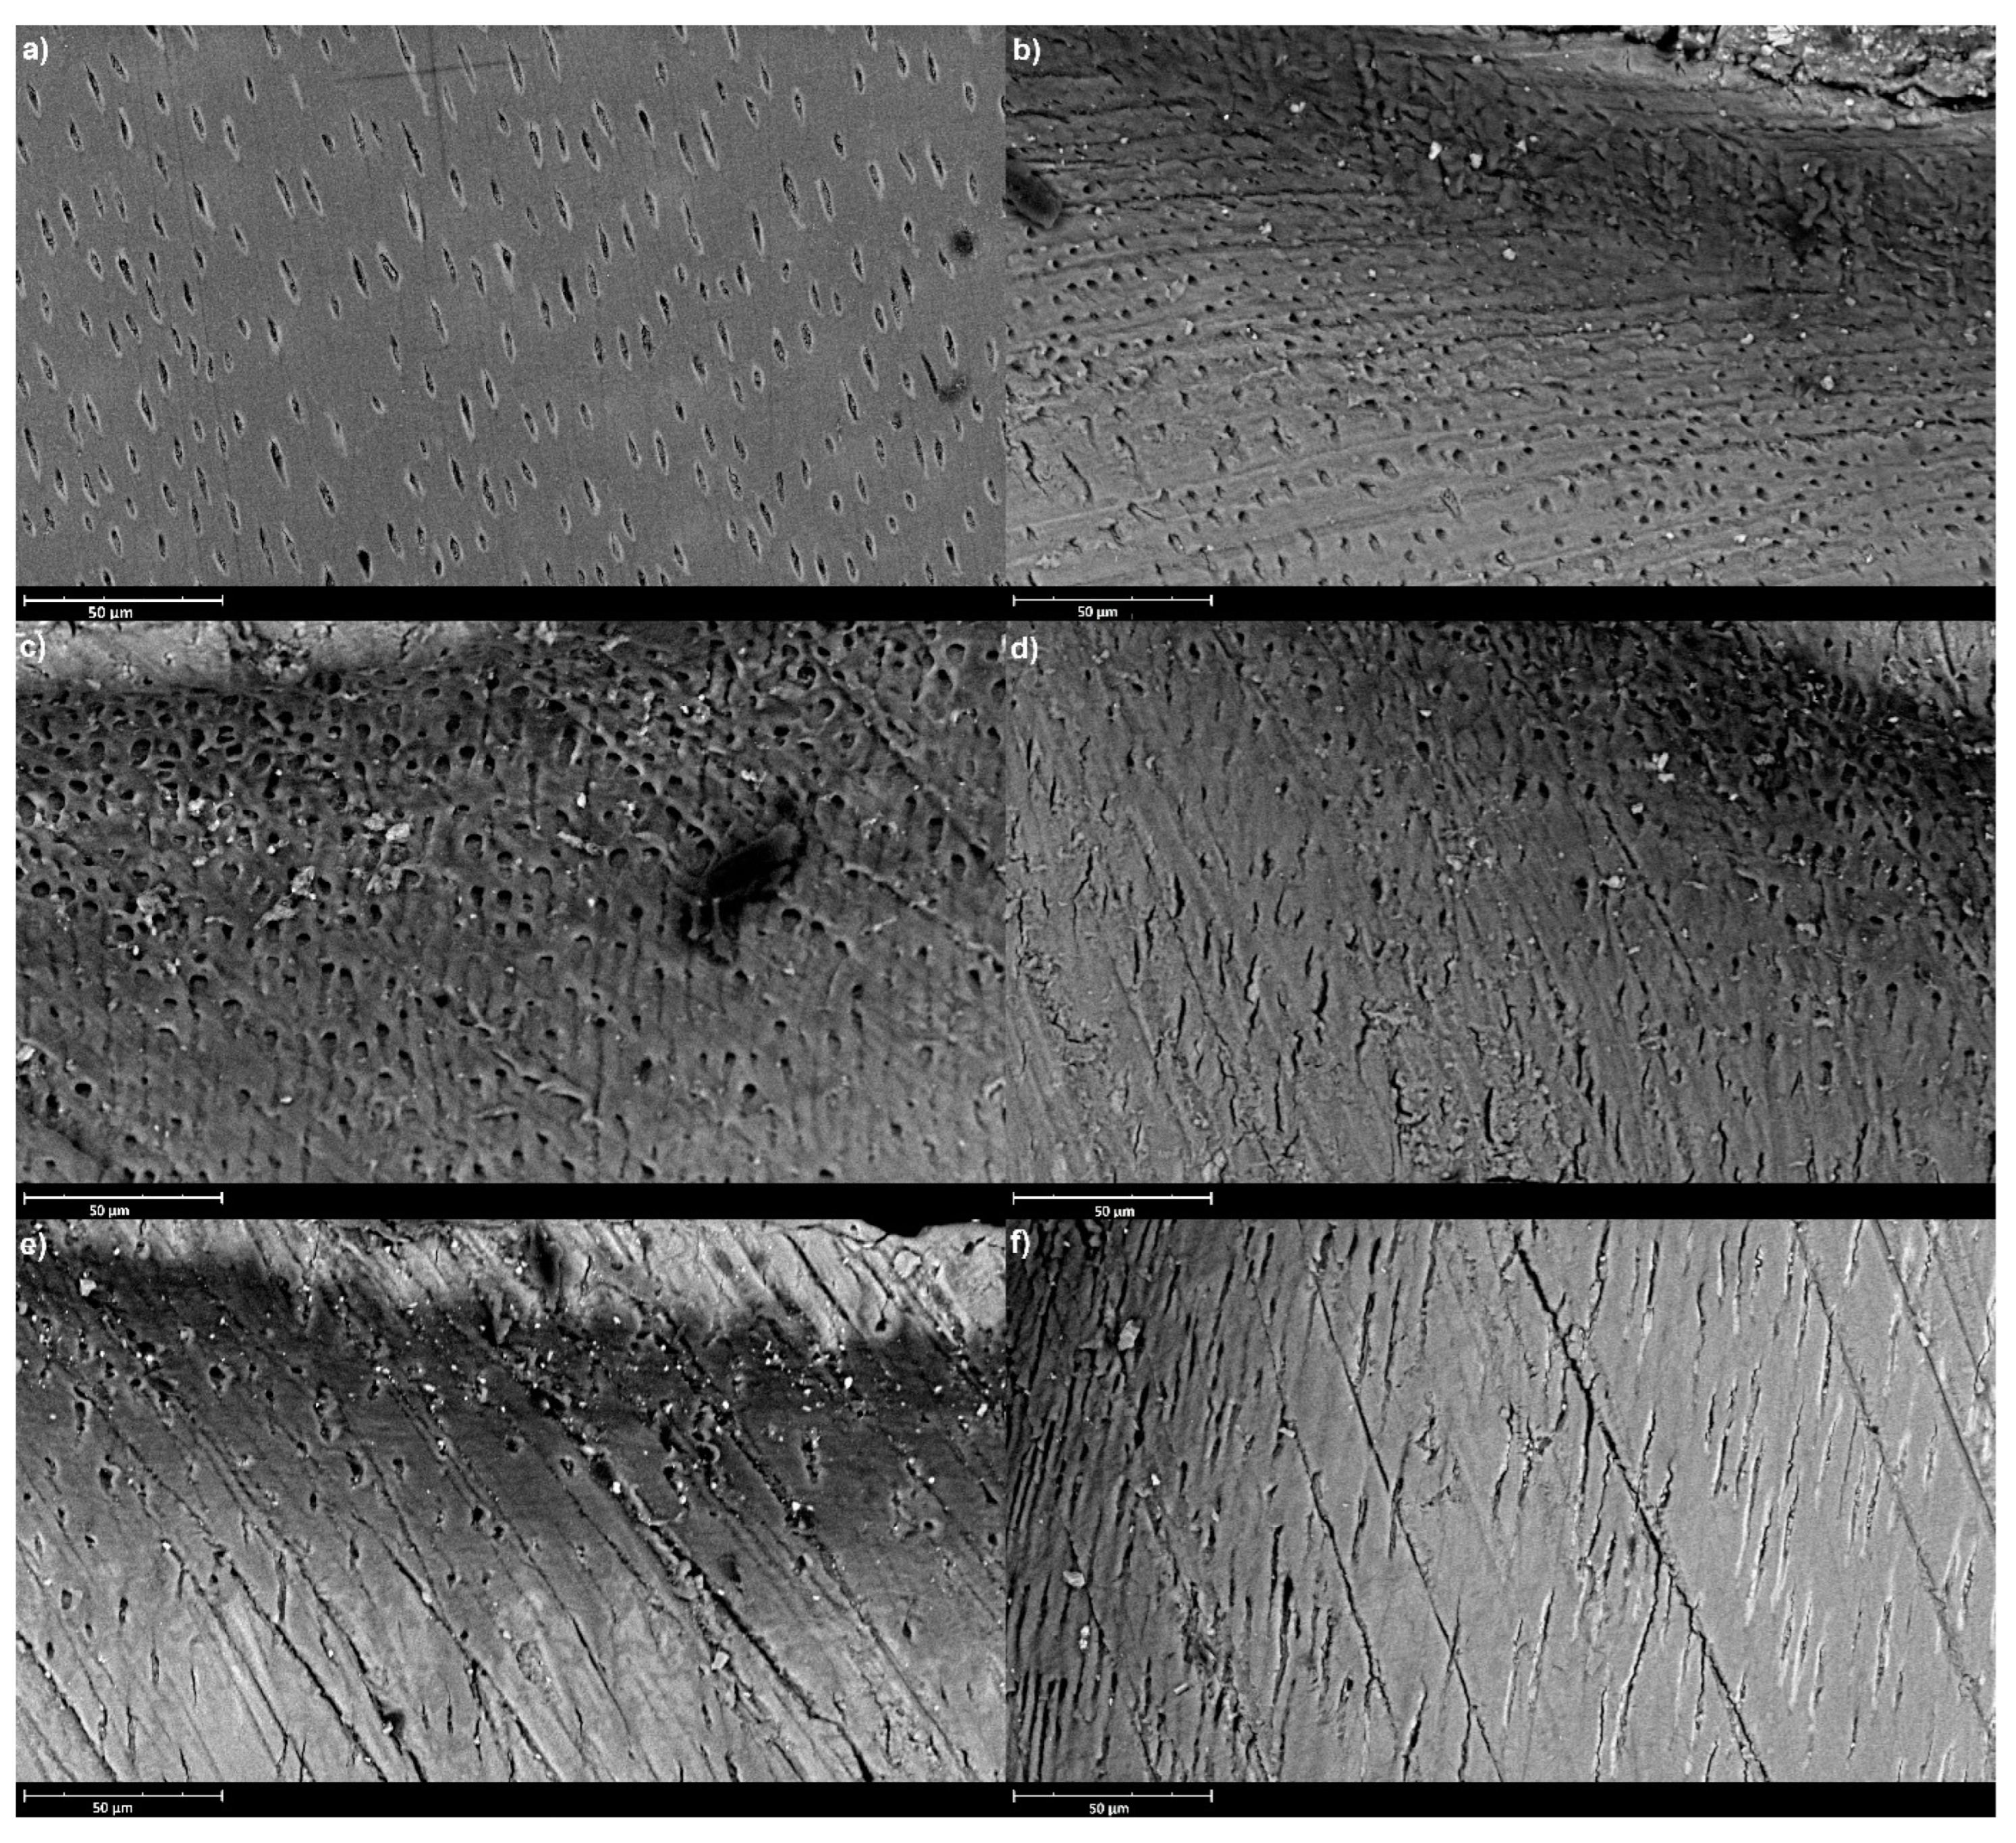

:1. Introduction

- There are no differences in the micro-surface appearance between groups.

2.3. SEM Analysis